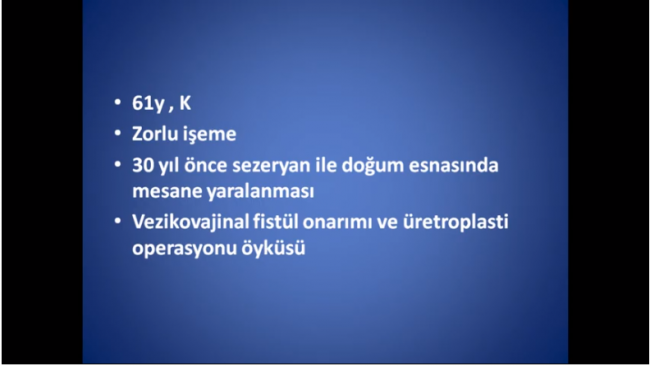

Notice: Trying to access array offset on value of type null in /home/u9176434/en.uretradarligi.com/wp-content/plugins/js_composer/include/autoload/vc-shortcode-autoloader.php on line 64 Notice: Trying to access array offset on value of type null in /home/u9176434/en.uretradarligi.com/wp-content/plugins/js_composer/include/autoload/vc-shortcode-autoloader.php on line 64 Notice: Trying to access array offset on value of type null in /home/u9176434/en.uretradarligi.com/wp-content/plugins/js_composer/include/autoload/vc-shortcode-autoloader.php on line 64 Ventral buccal mucosal urethroplasty ÖZGEÇMİŞ Yaş: 64…